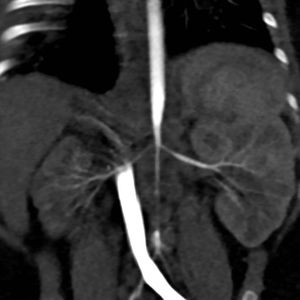

Caso 3PresentaciónUna lactante mujer de 4 meses de vida, con diagnóstico prenatal de miocardiopatía hipertrófica (atribuida inicialmente al cierre intraútero del ductus), ingresó en la Unidad de Cuidados Intensivos Pediátricos por una urgencia hipertensiva (PA domiciliaria de 180/110mmHg). En la exploración no presentaba pulsos femorales palpables y no tenía un soplo abdominal audible. Una gammagrafía renal y una angio-TC de aorta abdominal detectaron un riñón derecho pequeño e hipofuncionante (9,7% de función renal diferencial) y una disminución importante del calibre de la aorta abdominal por debajo de la arteria mesentérica superior, con estrechamiento del origen de las arterias renales (fig. 1).

Evolución clínicaSe inició tratamiento farmacológico (amlodipino y propranolol) y se derivó a un centro internacional de referencia, en el que se le practicó una angioplastia a los 6 meses de vida. Tras la misma, se objetivó una mejoría de la hipertrofia miocárdica. En la angio-TC de control se observó un aumento del calibre de las arterias renales (2,5 y 2mm respecto a 2 y 1,3mm previamente). A los 20 meses de vida se le realizó una nueva angioplastia. Actualmente, con 3 años de edad, presenta un buen control de la PA con un solo fármaco (atenolol).